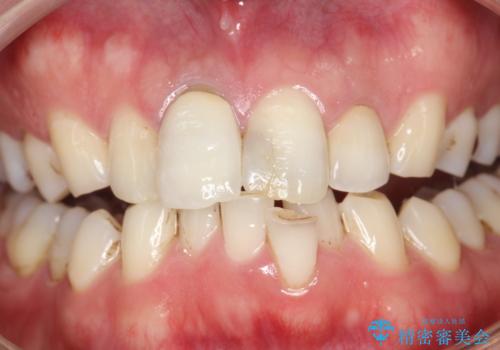

- 約3年ほど歯科医院での定期健診やクリーニングを受けてないとのことでした。全体的に歯石・着色などが付着していていたためPMTC60分コースを行いました。

分厚く歯石や着色が付着していると、汚れなのか虫歯なのかの判別がしづらい場合があります。しばらく定期健診やクリーニングを行っていない場合は、まずはしっかりと汚れを除去し、本来のご自身の歯の状態にすることで、より精密なお口の状態の診断が行えます。

PMTCによって、CRと、ご自身の歯の境目の着色などがしっかりと落とせて目立たなくなる場合と、PMTCによってしっかりとクリーニングを行うと、CR自体が古く劣化・変色などしていて目立ってくる場合があります。気になる際は詰め替えを行います。